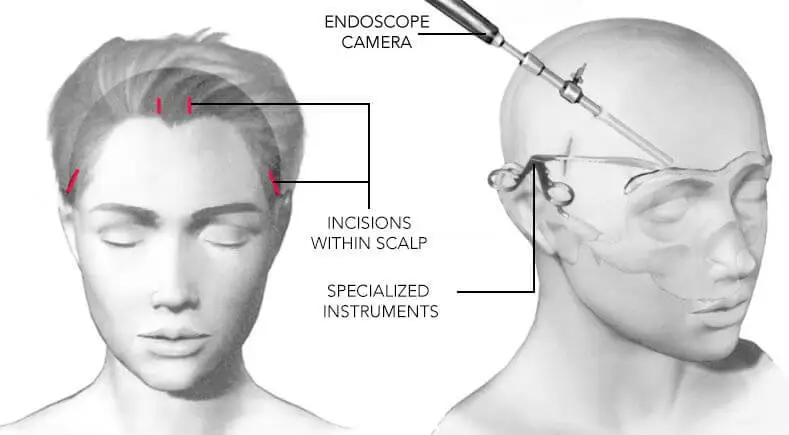

Brow Lifts

Price: Typically €3,000–€8,000 depending on the technique and clinic.Endoscopic Brow Lift

This is a minimally invasive method.Small incisions are made behind the hairline.

An endoscope is used to lift the forehead and reposition the brow.

The brow is secured with sutures or small fixation devices.

Pros:

Less scarring

Shorter recovery (1–2 weeks)

Good for subtle lifting and rejuvenation

Cons:

Slightly less dramatic lift than open methods

Requires specialized surgeon and equipment

More expensive than mini or temporal lifts

ENDOSCOPIC BROW LIFT BEFORE & AFTER

Price: €3,500–€6,000